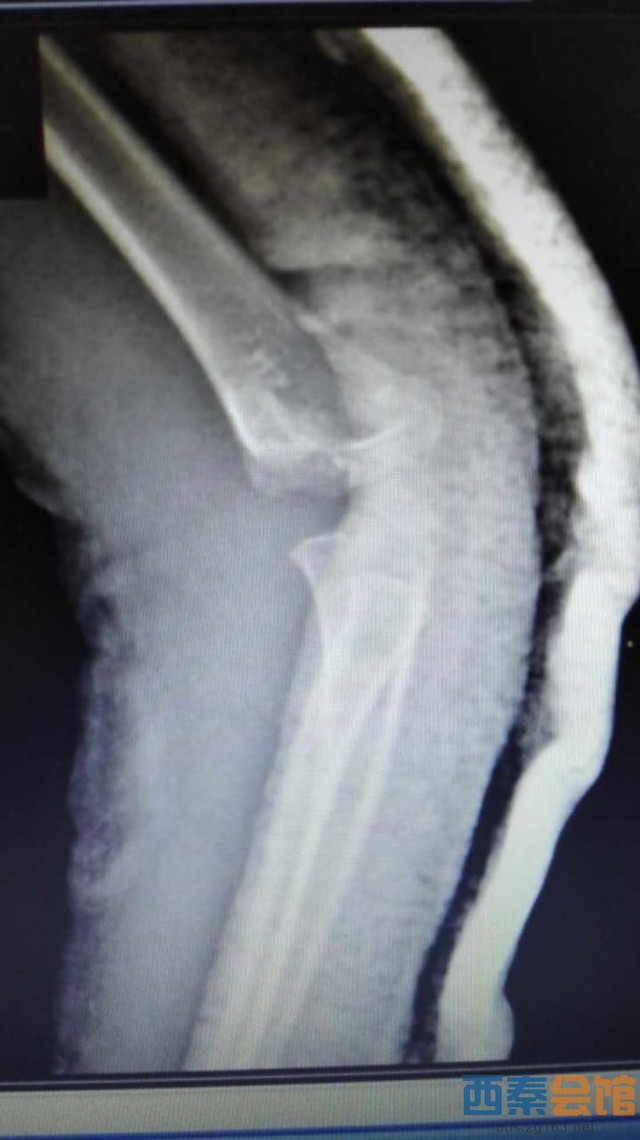

肱骨髁上骨折为儿童常见病,往往需要手术治疗,常规手术为做肘关节内外侧切口,交叉克氏针固定,手术创伤大,伤口瘢痕长,不美观等问题。市三医院骨一科梁涛主任根据患者需求,新引进儿童肱骨髁上骨折前路手术,仅3cm小切口切开复位后,于肱骨内外髁闭合穿针内固定,伤口皮内缝合,不需要拆线,术后伤口愈合快,术后4周可去除石膏托锻炼,术后6周可拔出克氏针,具有创伤小、美观、患者护理方便等优点。目前该5岁患者恢复良好,已出院休养。